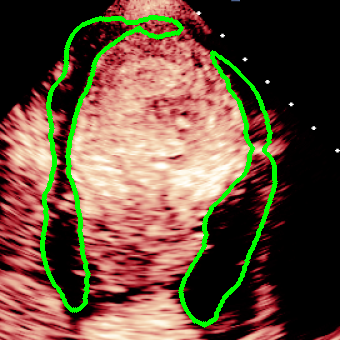

For variations caused by low quality images such as those of low resolution or significant artifacts, however, the unique ground truth may not be available. Take the myocardial segmentation task of Myocardial Contrast Echocardiography (MCE) as an example. An inter-observer experiment was conducted among five experienced cardiologists, and Fig. 1(a)(b) visualize the annotations of two images from three of these cardiologists. It can be seen that the labels by different cardiologists vary significantly, especially in locations where the intensity information of myocardium is very similar to the background. Table 1 shows the average Dice of the annotation of each cardiologist, using one of the others’ as the ground truth, over 180 images. We can observe that none of the Dice is above 0.9, some even under 0.8, confirming significant variations among the annotations. In this case, as the variations are caused by the image quality, even these cardiologists cannot tell which annotation is better than others, and a majority vote for ground truth would not make sense sometimes as can be seen in Fig. 1(c)(d). For this reason, we cannot obtain a unique ground truth in the evaluation process and the traditional metrics such as Dice and IoU cannot be used.